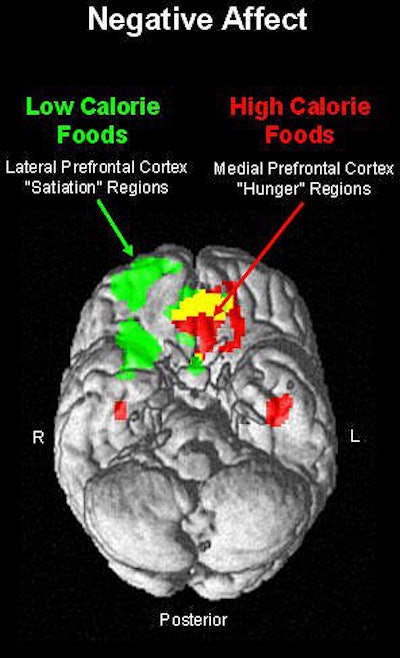

"The orbitofrontal cortex appears to be particularly important for evaluating reinforcement contingencies.... The experience of hunger and motivation to eat is associated with increased activity within the medial and caudal regions of the orbitofrontal cortex…. Lateral regions of the orbitofrontal cortex may serve as inhibitory function that leads the satiated individual to stop eating," wrote William Killgore, Ph.D., and Deborah Yurgelun-Todd, Ph.D., in the International Journal of Eating Disorders (July 2006, Vol. 39:5, pp. 357-363).

According to the results, the images of high-fat foods yielded greater fMRI activity within the right lateral orbitofrontal cortex, which correlated with PA subjective ratings. On the other hand, greater activation was seen within the medial orbitofrontal and insular cortex, along with higher NA ratings, when the participant looked at low-fat foods.

These results indicate that "functional segregation of the medial and lateral orbitofrontal cortex with regard to the motivation to eat," the authors stated, pointing out that the medial orbitofrontal cortex is associated with rewarding stimuli while the lateral orbitofrontal activity responds to punishing stimuli.

"The current findings … suggest that one mechanism of the relation between mood and appetite may involve the relative changes in brain activity within the lateral and medial orbitofrontal cortices," they wrote. As a result, people may go for high-fat foods in an effort to "self-medicate" their negative moods, the authors explained. Over a lifetime, this can lead to unhealthy food choices as a person's negative mood state drives her brain toward comfort foods, they added.